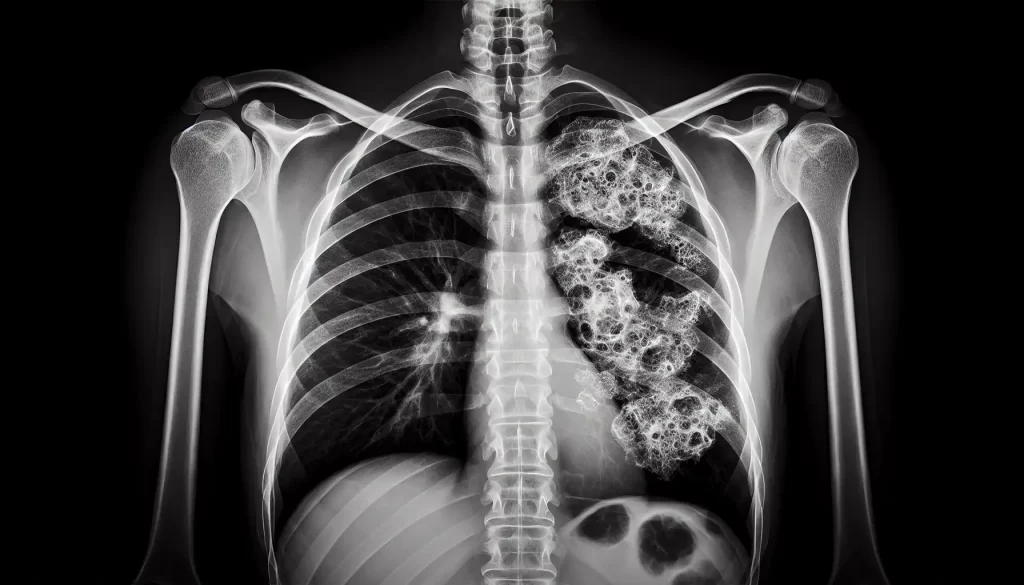

Doctors often turn to X-ray imaging as a starting move in the hunt for malignant pleural mesothelioma and other lung troubles. A chest X-ray doesn’t seal the deal on a mesothelioma diagnosis, but it does clue us into possible red flags that call for closer lookin’.

These X-ray snapshots show two-dimensional peeks inside the body, catching any weird bumps in tissues or bones hinting at mesothelioma. Common finds might include thickened pleural lining, plaques, extra fluid gathering in the pleural space, tumors, and other not-so-friendly growths hanging around the lungs.

But here’s the kicker, what you see on a chest X-ray isn’t unique to just mesothelioma. Those same telltale signs might point to other conditions like metastatic cancer, lymphoma, or even non-cancerous asbestos issues. So, while X-rays are a solid starting block, on their own, they can’t confirm mesothelioma for sure.

Mesothelioma X-rays tend to show some weird stuff that hints at this nasty cancer. Here’s what you might spot on one:

- Pleural Effusion: It’s fluid hanging out around the lungs, making things look cloudy on the X-ray.

- Pleural Thickening: When the lung lining gets thicker, it can mean trouble, like mesothelioma.

- Masses (Tumors): Look for strange growths or dense shadows, marking where the bad stuff’s at.

- Pleural Plaques: Those areas of thickened and calcified lung lining scream asbestos exposure.

- Obstructions: Tumors causing blockages that mess with how the lungs work.

It’s worth remembering these aren’t just mesothelioma signals. Other nasties like lung cancer can show up the same way. Often, docs will need to dive into CT scans, MRIs, and maybe even take a piece out for testing to really nail down the mesothelioma diagnosis.